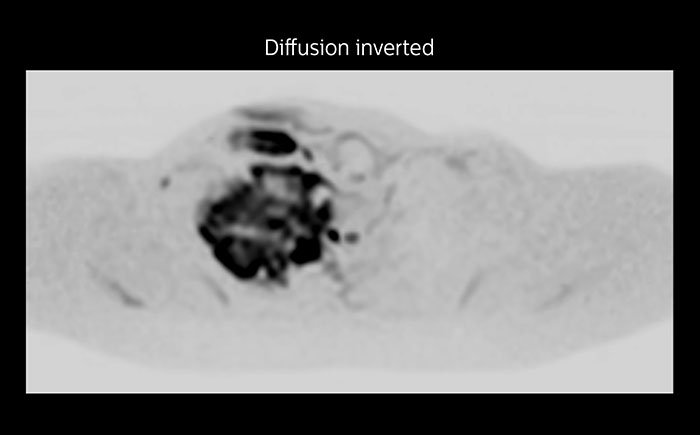

Whole body diffusion

A 61-year-old female with a malignant lymphoma underwent an MRI exam with whole body diffusion weighted imaging (DWIBS) as well as PET. On the images shown, the resolution of DWIBS is better than PET, which allows visualization of the small pelvic lesions and almost no distortion is seen in the neck area.

Prodiva MRI whole body DWI lymphoma, Seirei Mikatahara

Prodiva MRI whole body FDG-PET, Seirei Mikatahara